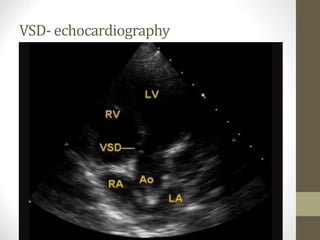

VSD- echocardiography